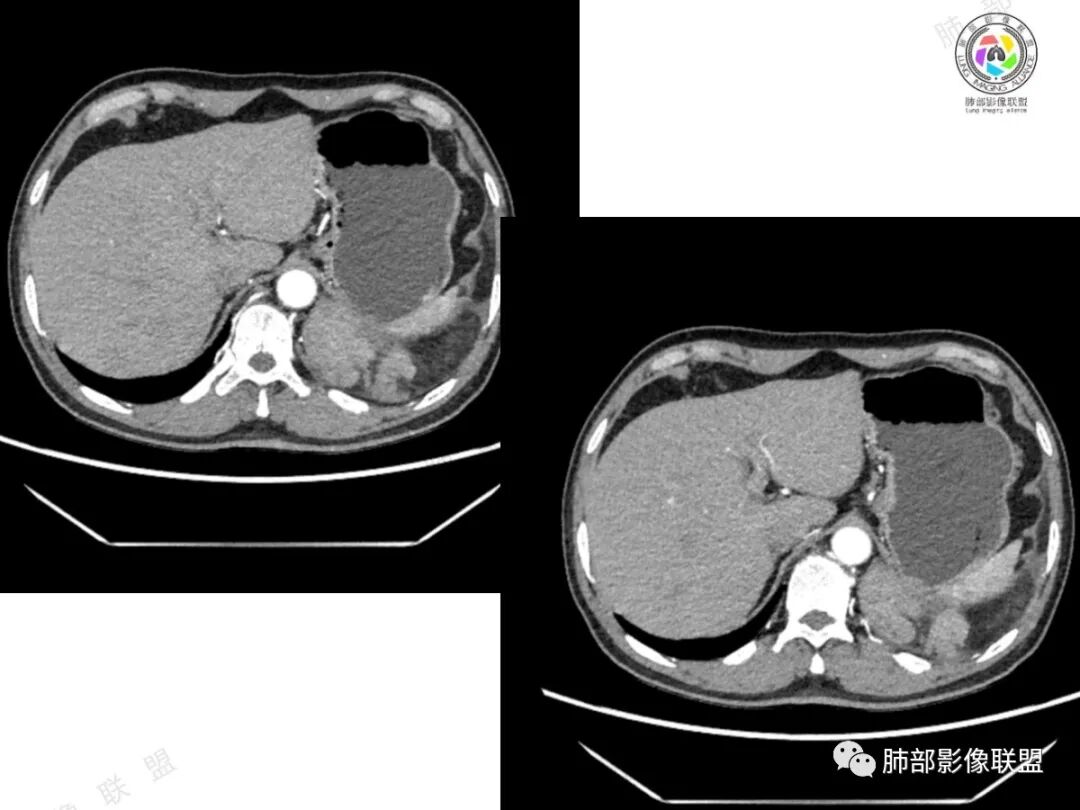

2、影像所见:左侧纵隔紧贴心包铸型生长巨大混杂密度肿块,边界清楚,临近结构受推挤移位,无明显外侵征象。肿块自主动脉弓旁一直顺延到至膈顶,呈“垂乳征”。病灶脂肪成分居多,斑片状、结节状及团块状实性密度成分散落其中,呈地图样分布,实性成分偶见低密度线样分隔,未见明确钙化影。增强扫描实性成分呈延迟明显强化,并见强化血管影。纵隔内有肿大淋巴结,未见胸腔积液,肺内及胸膜未见转移性病灶。

①脂肪肉瘤:本例含较多脂肪组织,需考虑分化成熟型脂肪肉瘤(高分化型)的可能,其好发于前中纵隔的下部及心膈角区,肿块常大,偏于一侧,可有分叶,包膜可完整,与周围组织器官界限清楚。以脂肪密度为主的肿块,增强后仅见间隔或实性部分轻微强化。而本例实性成分过多,且实性病灶强化较明显,与高分化型脂肪肉瘤表现矛盾。

②胸腺脂肪瘤:好发于前下纵隔心膈角区,肿块一般较大,多见于40岁以下年龄患者,其内可见条状或片絮状胸腺组织,一般无周围侵犯。本例实性成分多、体积大,年龄较大,与胸腺脂肪瘤存在较多冲突。